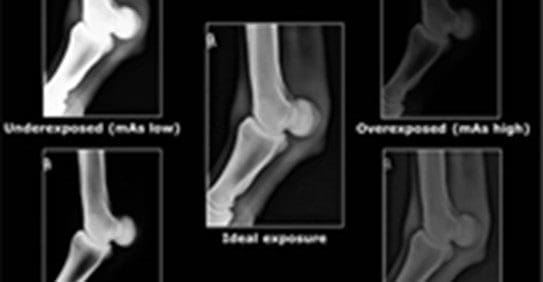

It is essential that radiographs taken in practice should be of diagnostic quality to enable accurate evaluation for the presence of disease/pathology.